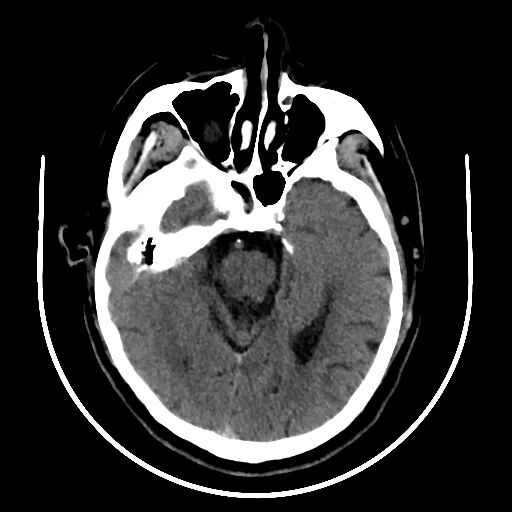

查体BP 160/89mmHg,清醒,双眼左侧凝视位、不可纠正,混合性失语,右侧中枢性面舌瘫,右侧肢体肌力0级,右侧病理征阳性。NIHSS评分18分。随机血糖4.8mmol/L。心电图:正常。颅脑CT无出血及新发梗死灶,多模态CT示左侧大脑中动脉闭塞、左侧大脑半球低灌注。

术前检查

颅脑CT无出血及新发梗死灶。